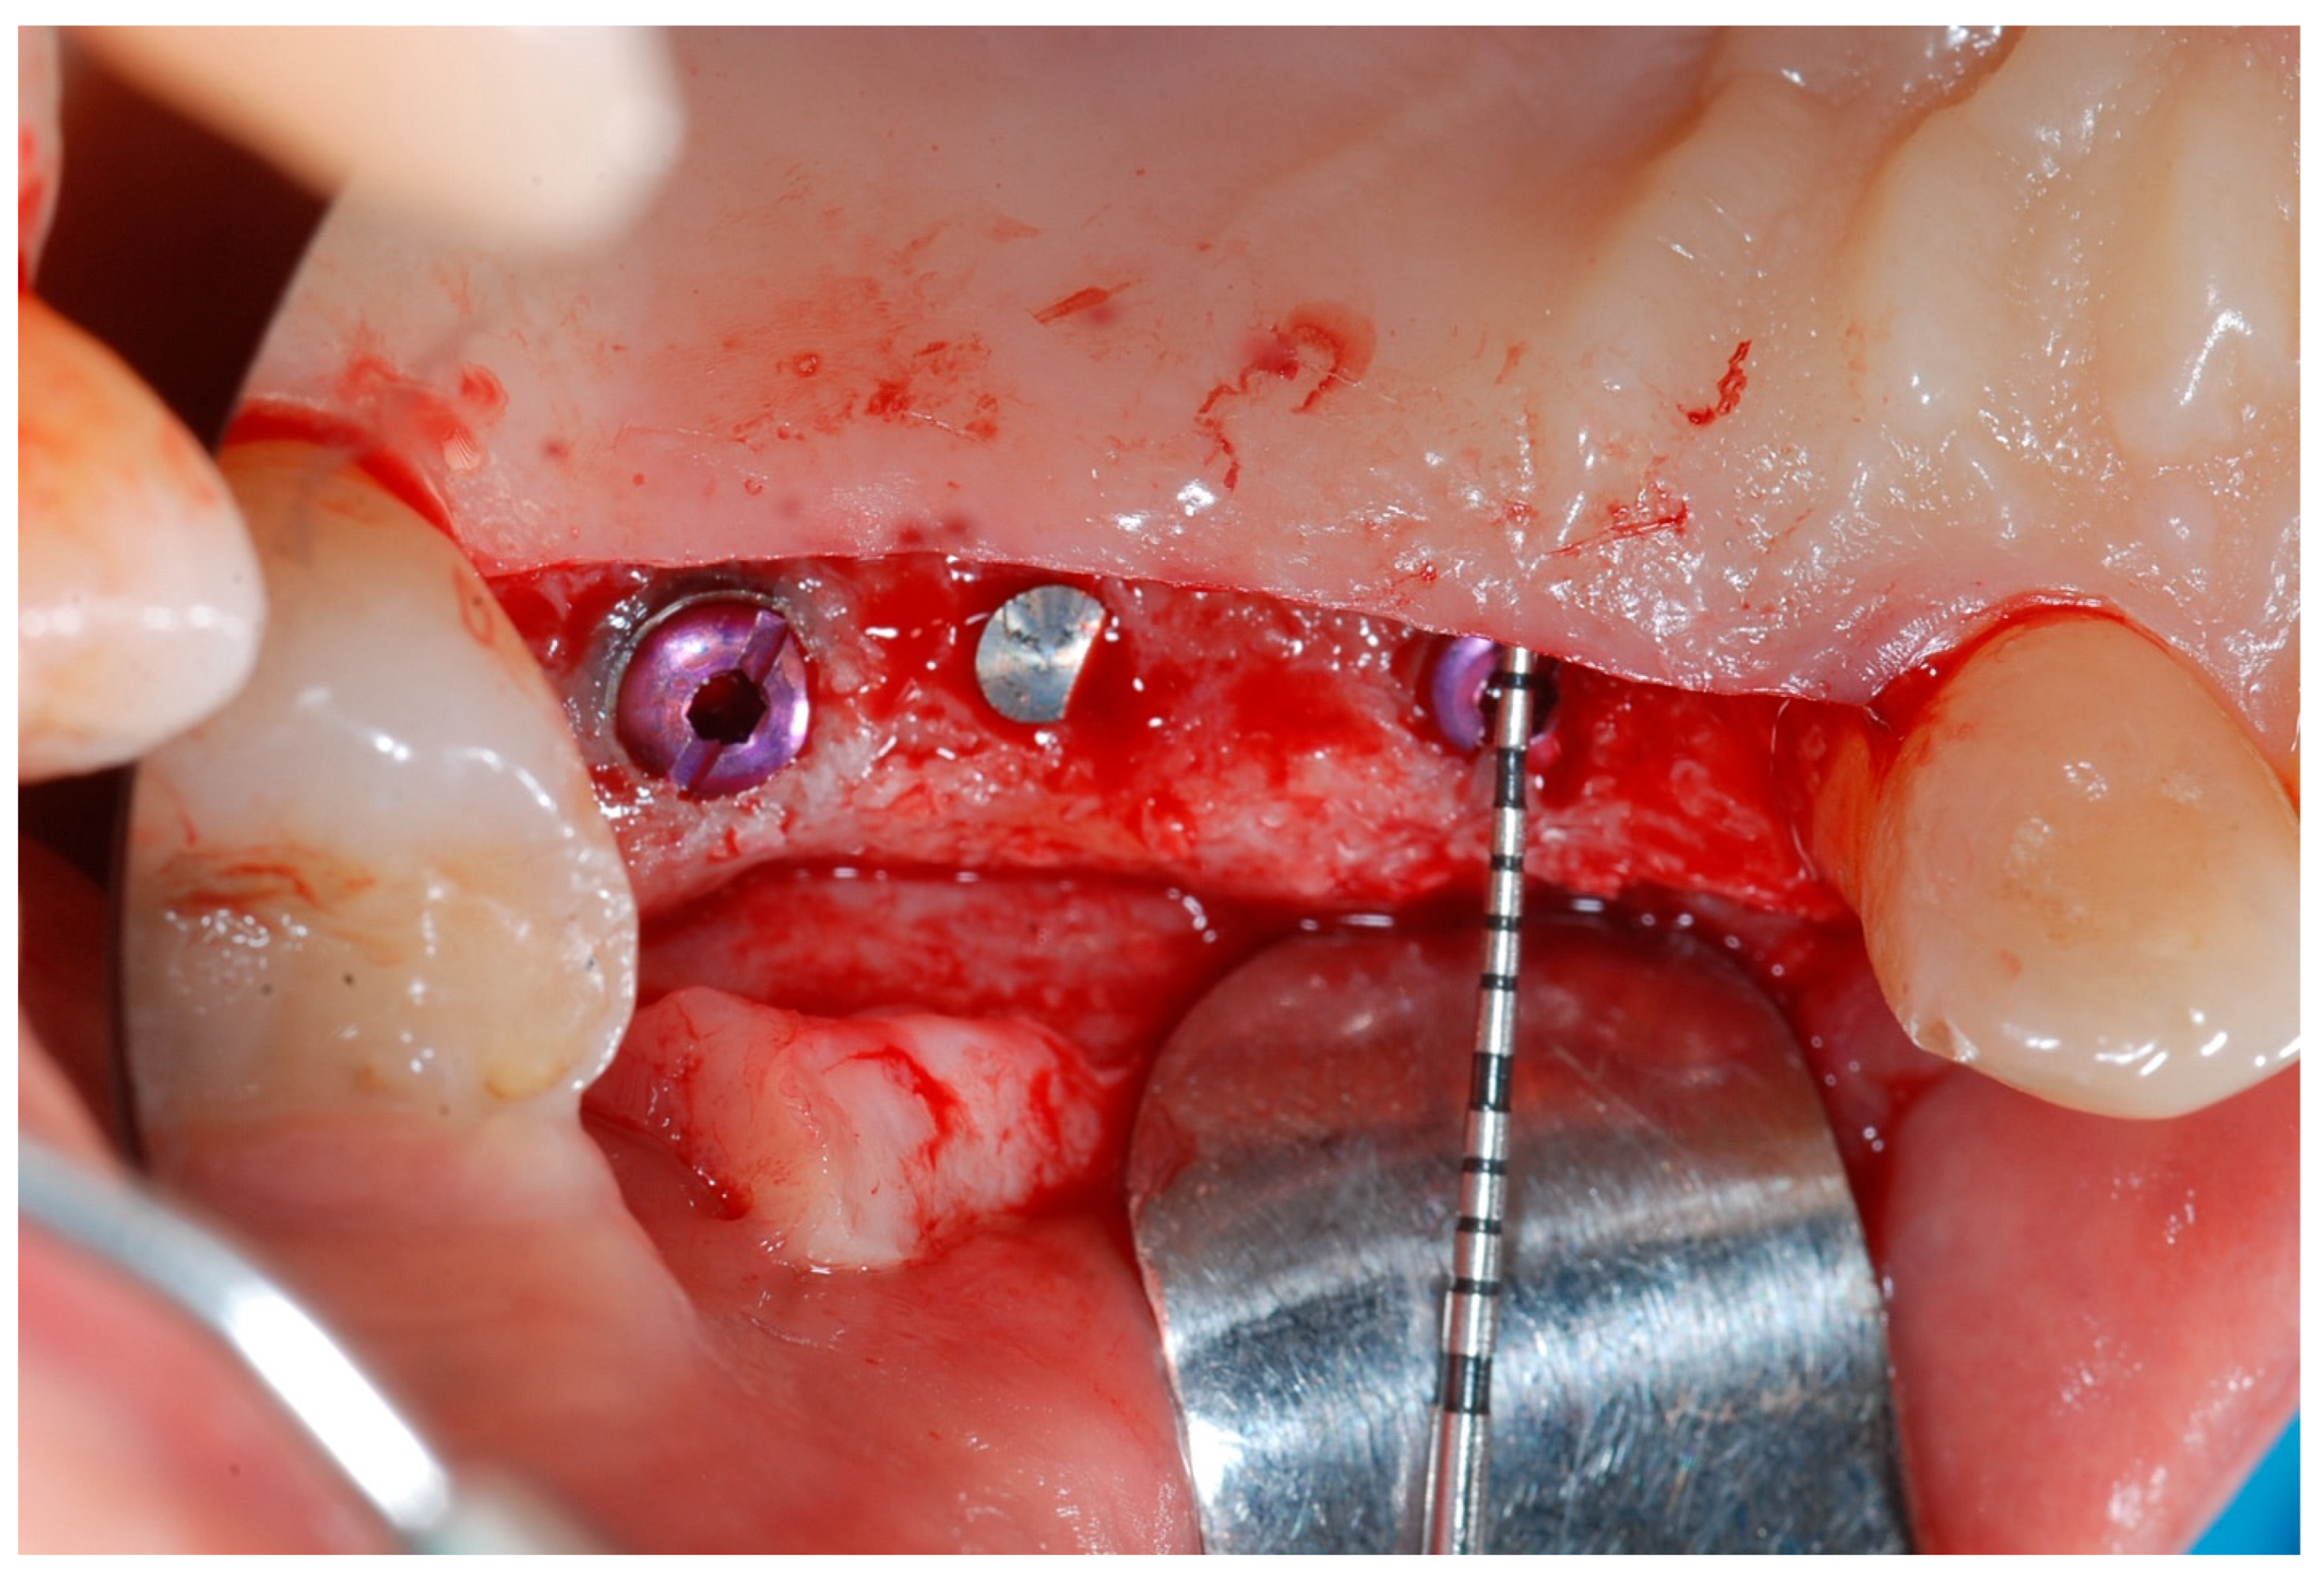

Local anesthesia was obtained with mepivacaine 20 mg/mL with epinephrine 1:100.000 (Optocain, Molteni Dental, Milan, Italy) injections. To raise a mucoperiosteal flap, a crestal incision followed by oblique releasing incisions were made to allow for a wide flap basis as well as sufficient access to the defective ridge area. The flaps were carefully raised using tissue elevators. The bone ridge was examined and any soft tissues remaining on the crest were meticulously removed with a surgical curette (Figure 2).

Figure 2. Trapezoidal flap elevation and initial bone thickness.